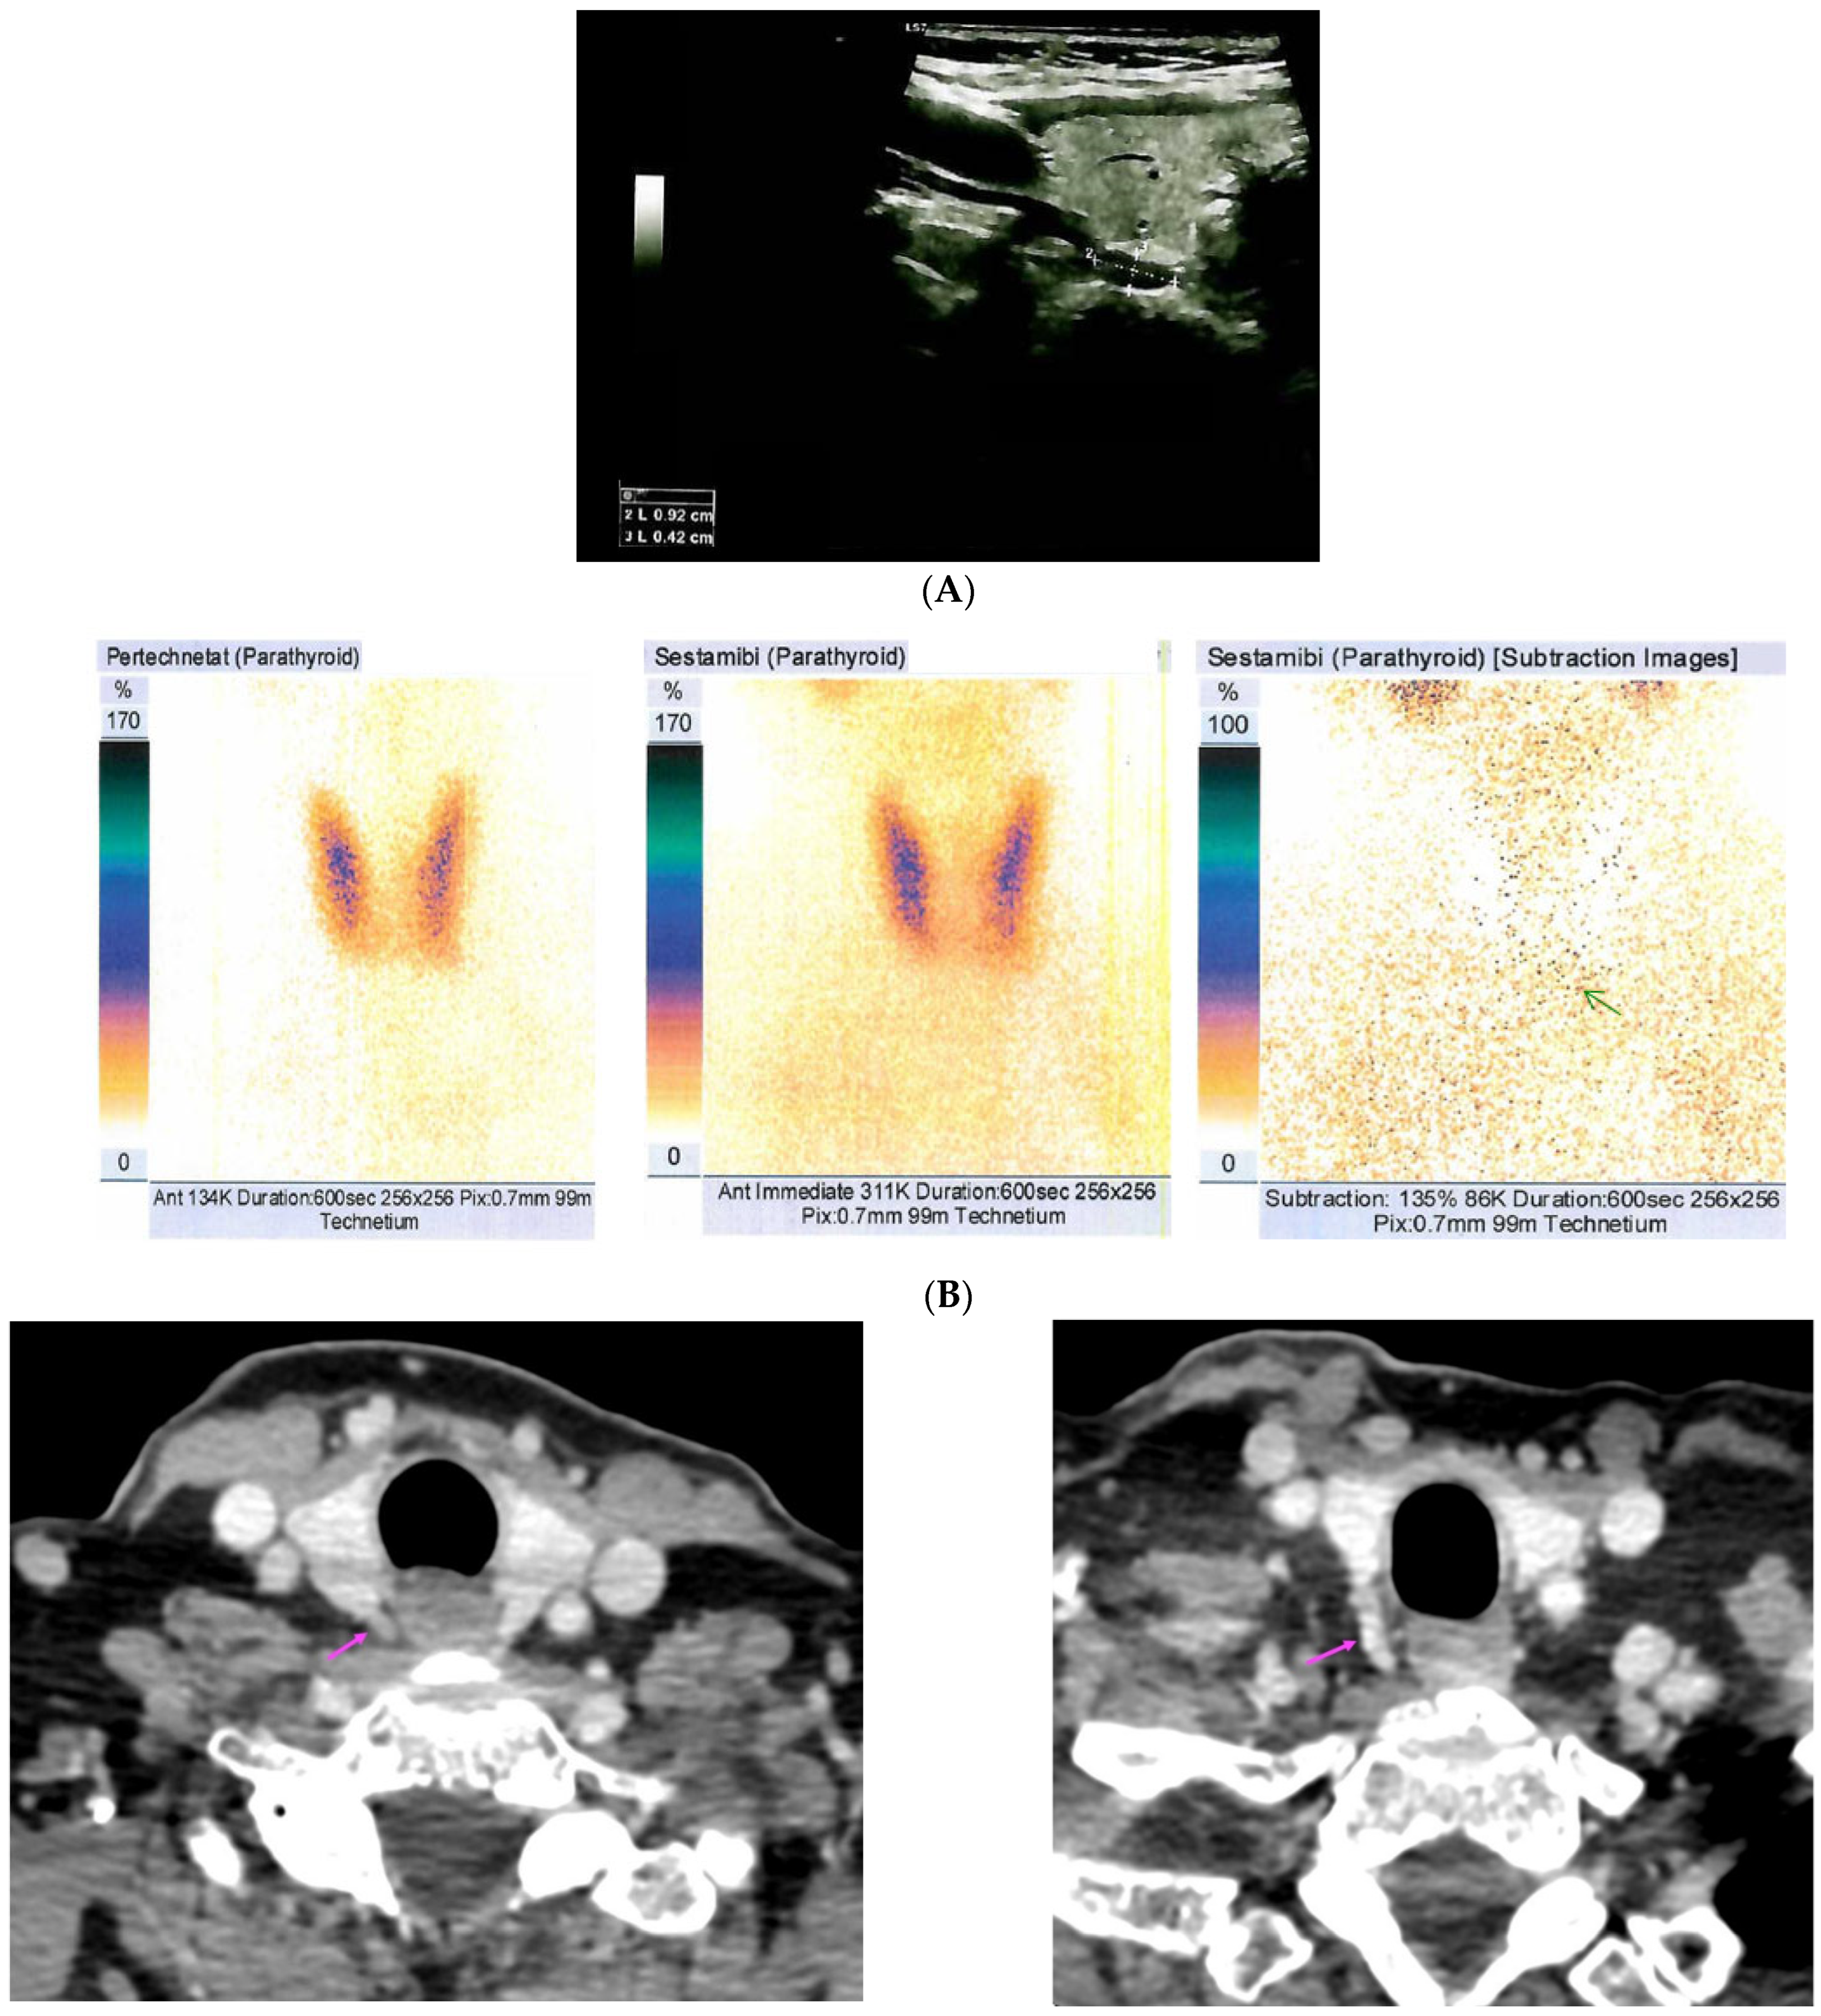

| Reference | Imaging Evaluation | Pathology Report |

|---|---|---|

| [37] | US: six nodules of 5 mm to 16 mm located subcutaneously anterior of right sternocleidomastoid muscle 99m-Tc sestamibi scintigraphy: no hyper-functional foci CT: similar to US | Parathyromatosis |

| [38] | 99m-Tc-MIBI imaging (SPECT/CT): three foci of elevated uptake on early phase with slow washout on delayed phase | Hyperplastic parathyroid tissues |